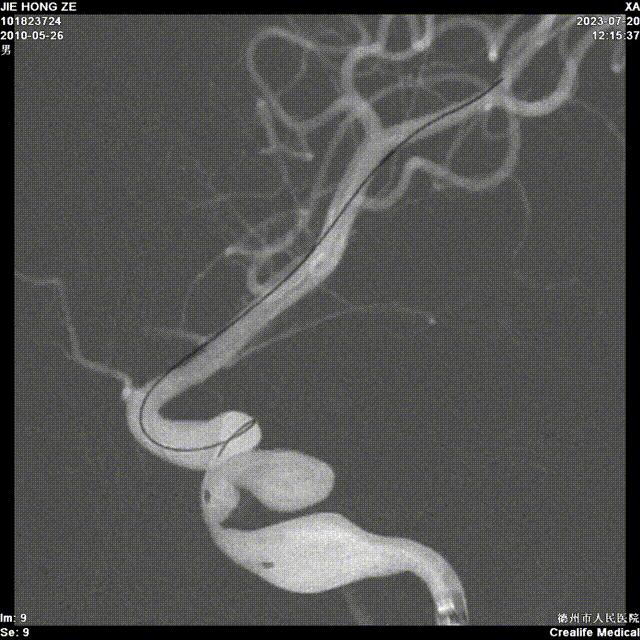

现病史:2个月前因高血压到济南齐鲁医院检查治疗,期间行颅脑MRA检查提示左侧颈内动脉海绵窦段动脉瘤,为求进一步诊治来我院,门诊以“颅内动脉瘤”收入院。

左侧颈内动脉海绵窦段动脉瘤。

- 左侧颈内动脉海绵窦段动脉瘤,累及海绵窦全程,远端一段小梭形夹层,中段一个囊状动脉瘤,近端一段大梭形夹层,中间还有一处重度狭窄。

- 整个病变较长,预计病变长度60mm 进行覆盖,支架最长型号40mm,选择大直径还是进行桥接?

术前造影: